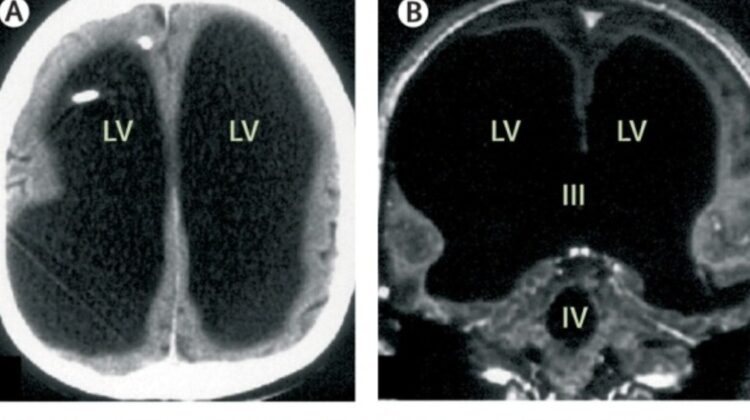

First documented in the medical journal The Lancet in 2007, the case involved a middle-aged man whose brain scans revealed something extraordinary—most of his skull appeared to be filled with fluid, leaving only a thin layer of brain tissue.

He only sought medical help after experiencing mild weakness in his leg. What doctors found during imaging was unexpected: his brain had been severely compressed over decades.

The condition behind this was hydrocephalus—a disorder in which fluid accumulates in the brain. He had been diagnosed as an infant and treated, but after the removal of a shunt in his teenage years, the fluid gradually built up again.

Early interpretations of the case suggested that up to 90% of his brain was “missing.” Later clarification showed that the brain tissue was still present—but squeezed into a thin outer layer.